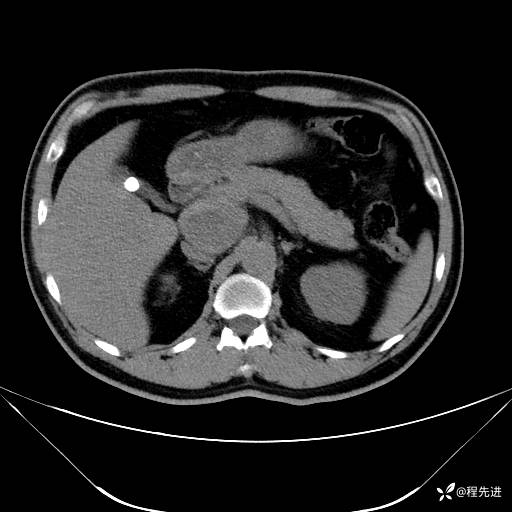

【腹盆】特别精彩病例|发现腹膜后肿物1月余

患者性别:男

患者年龄:42岁

主诉:发现腹膜后肿物1月余

现病史:患者1月余前查体,行超声检查提示:后腹膜囊实性肿块;慢性胆囊炎伴胆囊内结石;无腹痛腹胀,不伴腹泻发热等;偶感腰背部酸痛。

实验室检查:乙肝表面抗原(+),乙肝e抗体(+),乙肝核心抗体(+)

CT平扫+增强: